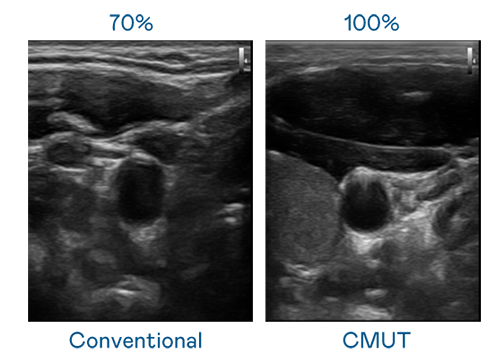

CMUT 技术是一种用电容式微机电元件来产生超音波讯号的技术。与传统 PZT 压电式技术相比,CMUT 频宽增加 30%,更宽频的超音波讯号让影像解析度大幅提升,是实现高影像品质医疗超音波扫描、促进精准医疗发展的关键技术。

大频宽带来超清晰影像

超音波影像的解析度高低,首先取决于探头能发出的讯号频宽。爱游戏网页版官方入口 CMUT 可提供高清晰的超音波讯号,提供高频宽、高灵敏度、影像纹理细节更高的超音波影像,协助医护人员缩短影像判读时间及利用精准的医疗影像进行诊断。